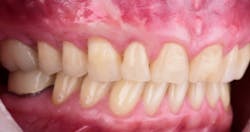

This new biological approach involving blood derivatives A-PRF and I-PRF combined with precision minimally invasive surgery for root coverage demonstrates faster healing without the need of a donor site. The morbidity of GDT is decreased and patient case acceptance is higher compared with traditional grafts. Before-and-after pictures are shown below (figures 15–22).